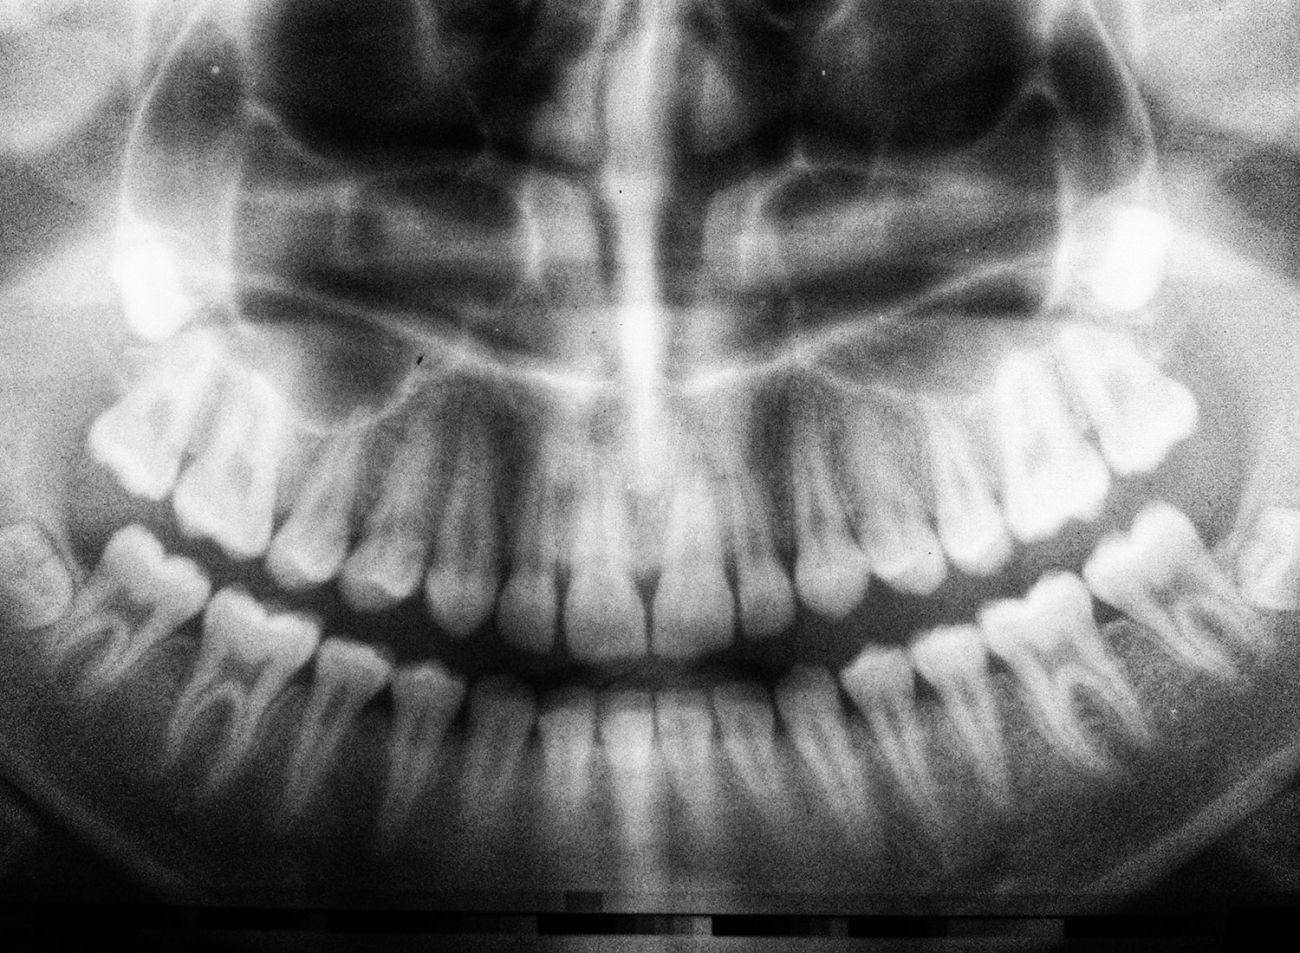

Nach aktueller röntgenologischer Untersuchung, können wir auch für Sie die bestmögliche Versorgung mit Implantaten planen!